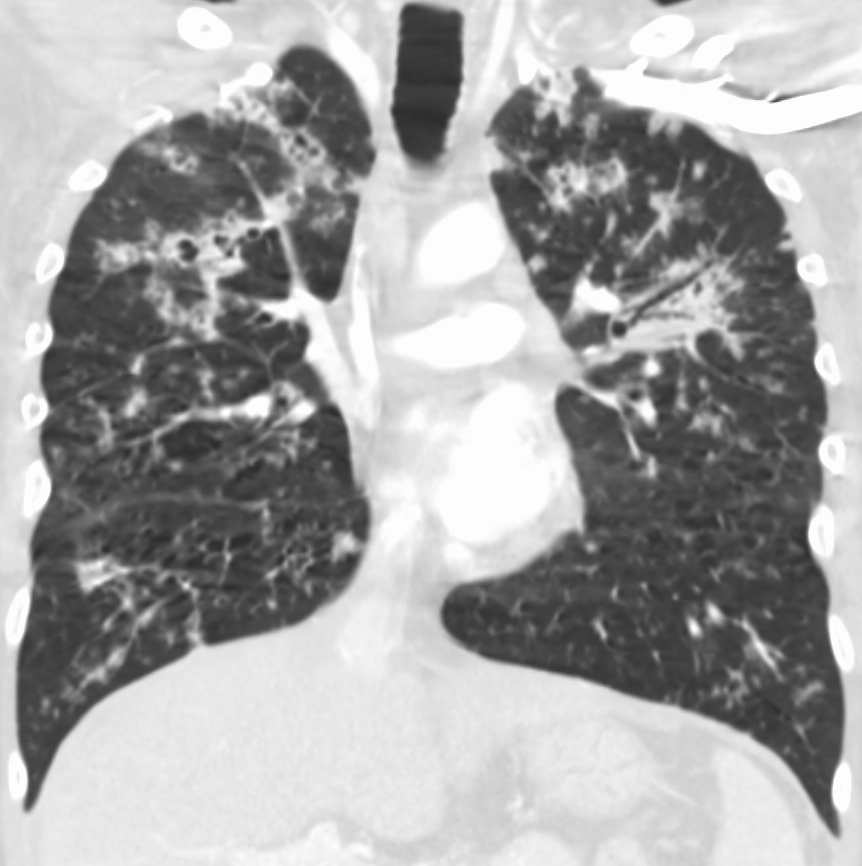

4. 진단

속립 결핵의 진단은 다른 형태의 결핵과 같은 방식으로 진행되지만, 확진을 위해 여러 검사가 필요하다.[4] 여기에는 흉부 엑스레이, 객담 배양 검사, 기관지 내시경 검사, 개방 폐 생검, 머리 CT/MRI, 혈액 배양 검사, 안저 검사, 심전도 검사가 포함된다.[10][22] 인터페론 감마 분비 검사(IGRA)라고도 하는 결핵 혈액 검사는 잠복 결핵을 진단하는 방법이다.[10]

드물게 폐암의 림프관 전파가 일반적인 흉부 X-선에서 속립 결핵 패턴을 모방할 수 있다.[15]